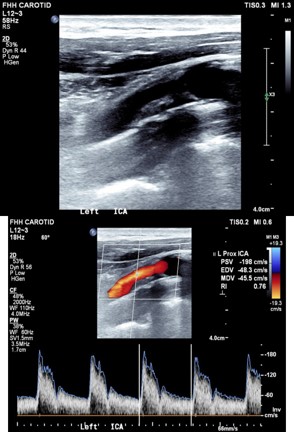

In the emergency room, his vitals indicated hypertension, with otherwise stable parameters. His EKG showed normal sinus rhythm at 73 bpm with an incomplete left bundle branch block. Carotid Doppler and CT angiography of the neck revealed 69% stenosis of the left carotid artery as shown in Figure 1 above, and less than 20% stenosis of the right carotid artery (Figure 2). He was started on Plavix and maintained on oral doses.

Figure 1: Showing a 69% stenosis of the left carotid artery with high flow velocity.